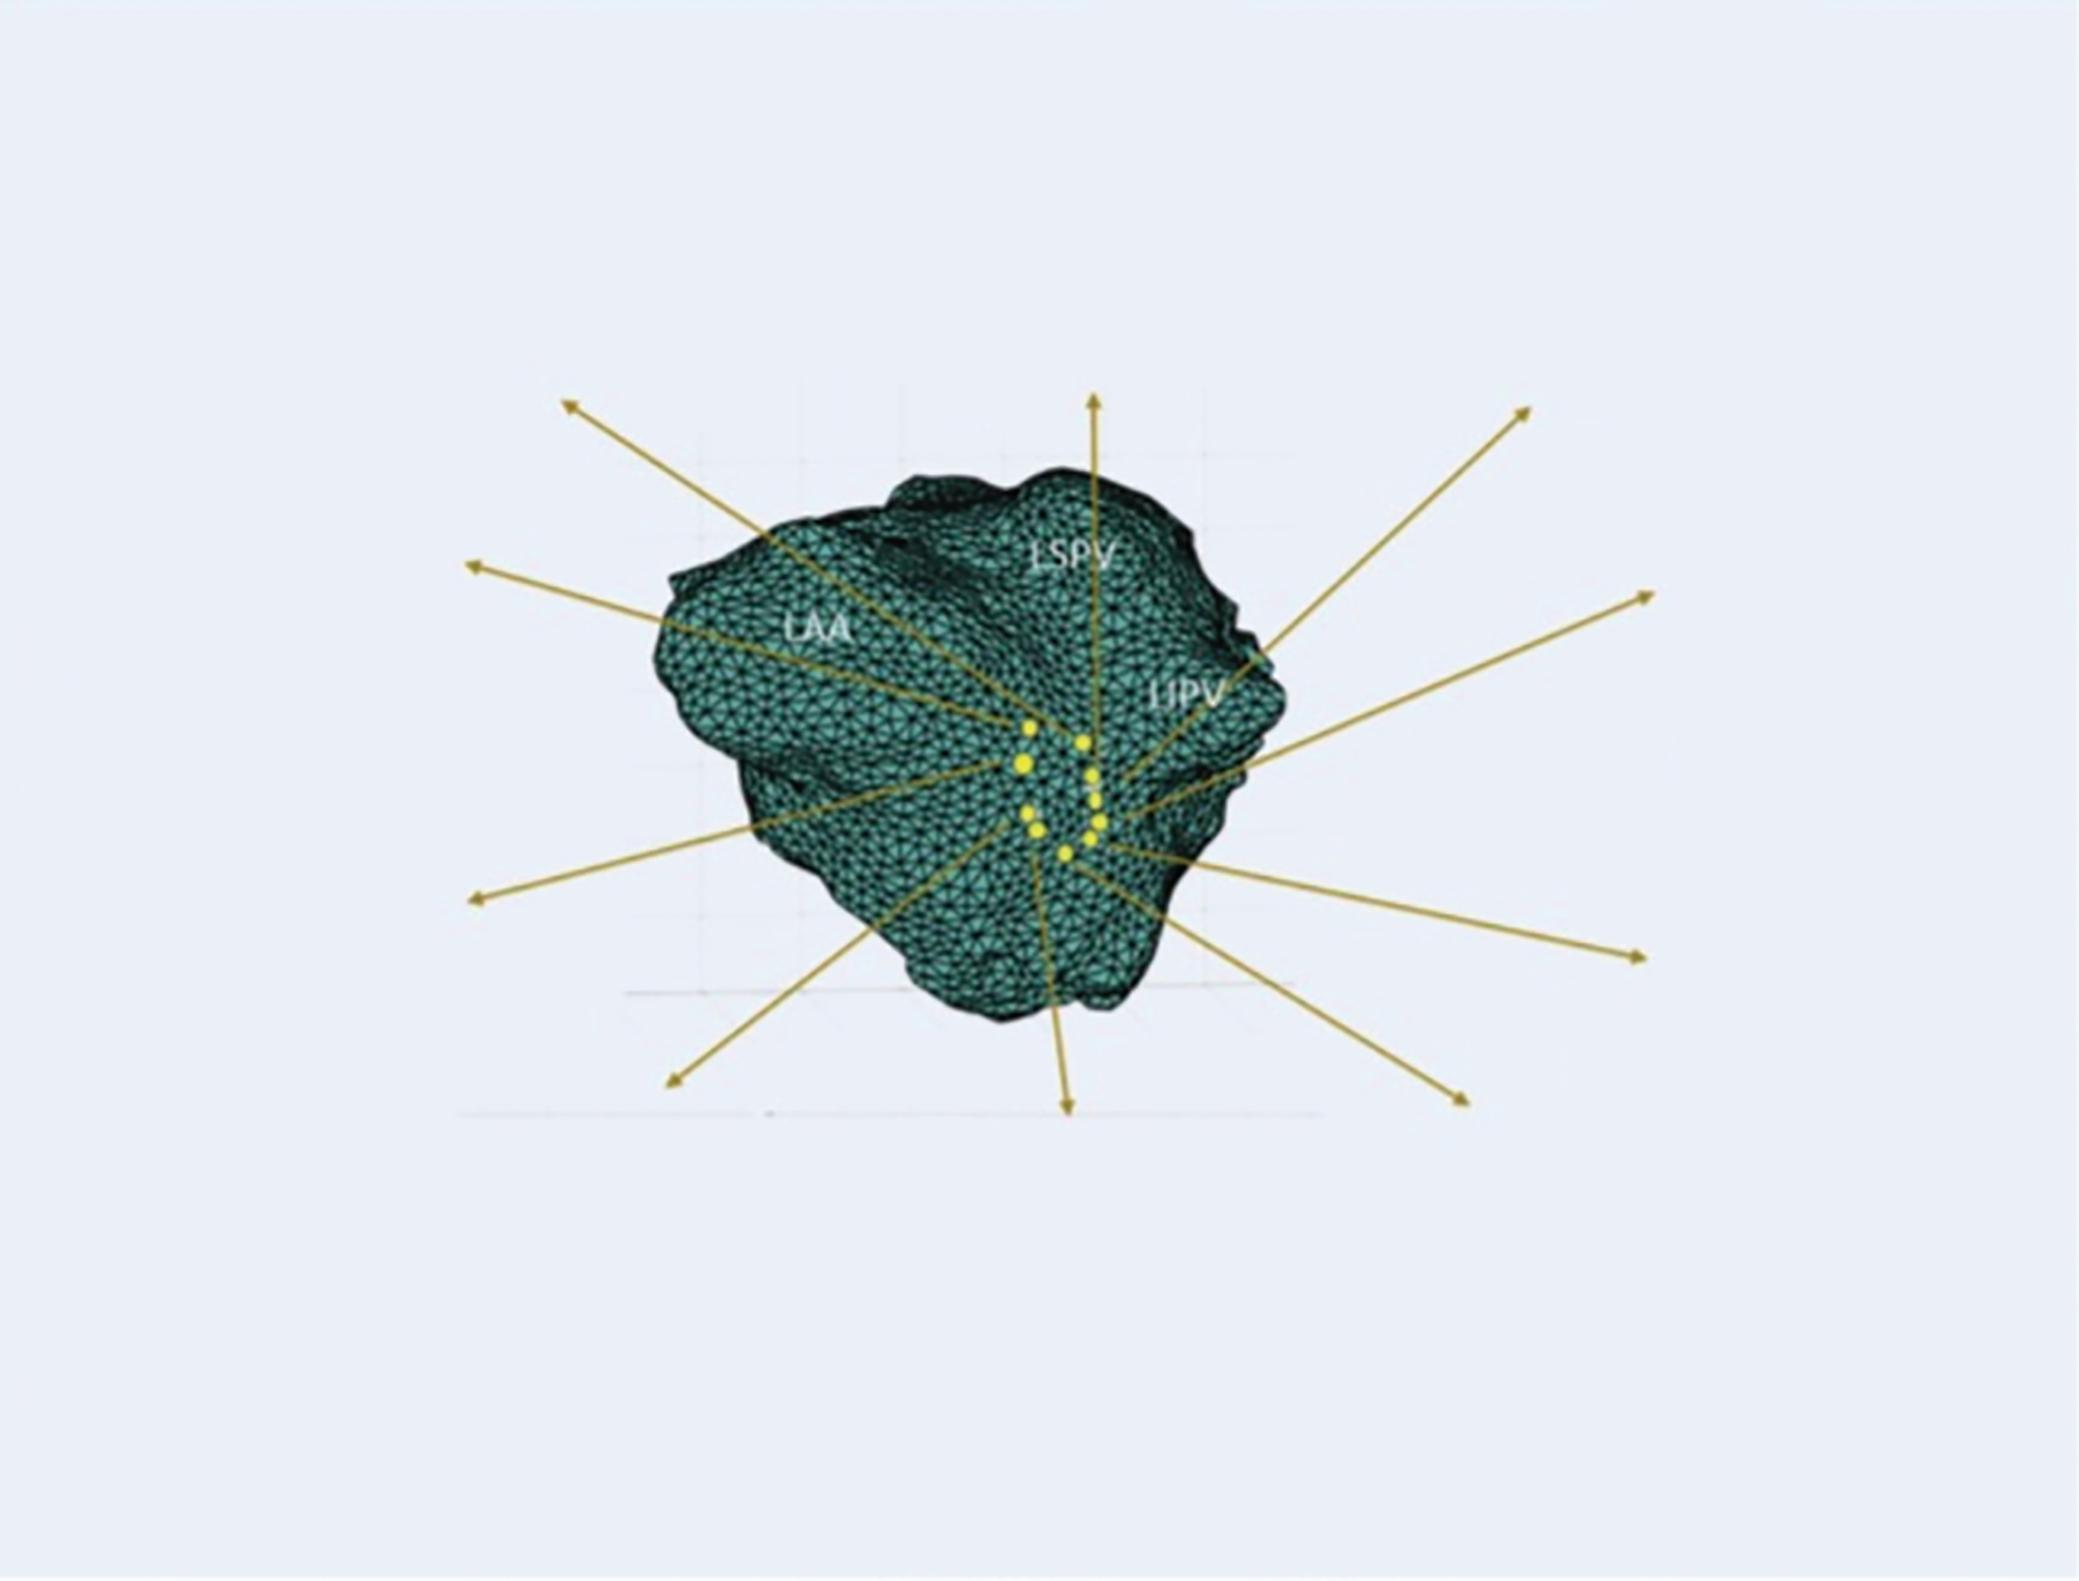

Figure 7: Assessing Elimination of Arrhythmogenic Fibrotic Substrate by Late Gadolinium Enhancement-MRI

Against this background, we have recently analysed the potential role of LGE-MRI to assess the long-term effect of VT ablation in terms of arrhythmogenic substrate elimination (unpublished data). Three to 6 months following the procedure, effective ablation was reflected by pronounced reduction of LGE-MRI-detected border zone scar volume and extent of slow conduction channels compared to the preprocedural LGEMRI (Figure 7). In patients undergoing repeat ablation procedures, this arrhythmogenic substrate elimination as determined by LGE-MRI correlated well with EAM. Thus, LGE-MRI-based lesion assessment may be of potential value to evaluate the efficacy of ventricular substrate ablation and to predict VT recurrences and clinical outcome. However, as mentioned above, clinical validation is warranted.

Left panel: LGE map of the left ventricle prior to substrate-based ventricular tachycardia ablation. LGE depicts an antero-apical scar. A 3D-analysis using the ADAS 3D software predicts a slow-conduction channel (black line) extending over 30 % of the transmurality that was confirmed by invasive electroanatomical mapping. Right panel: LGE map of the left ventricle 3 months post-ventricular tachycardia ablation. LGE indicates complete scar homogenisation and ‘dechannelling’ with ablation lesions covering the full substrate. Percentages indicate distinct layers of the transmurality from endocardial (0%) to epicardial (100%). LGE = late gadolinium enhancement.